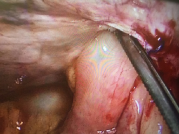

Contrast-enhanced CT was not done as the condition was very obvious clinically. He was taken up for diagnostic laparoscopy under general anesthesia which showed herniation of distal small bowel loop through a peritoneal defect of the previous hernioplasty site with dense adhesions of the bowel to the mesh .The herniated bowel was reduced, the hernia defect was dealt with closure by direct stitching and glue again of the mesh to the abdominal wall after aspiration of the reactionary fluid, stitching itself was not an easy task because of the friability and thinness of the peritoneal flap and this is why a glue is used. The patient had an uneventful recovery and was discharged on the fourth post-operative day. The patient underwent follow-up examination 21 days after discharge and did not have any significant abnormality.1–3

In our case, the patient had a sutured closure of the peritoneal flap after a laparoscopic TAPP mesh hernioplasty. He presented 7days after the surgery with features of intestinal obstruction. The herniated loop of bowel through the peritoneal defect was densely adherent to the mesh and it was managed again laprascopically. The Guidelines of International Endo Hernia society8 recommends thorough closure of the peritoneal defect in TAPP to decrease the risk of bowel obstruction (Level 3 Grade C) and running absorbable suture as an appropriate method to close the defect (Level 5 Grade D) (Figures 1-5).9

Figure 5 Small bowel loops adherent to the mesh